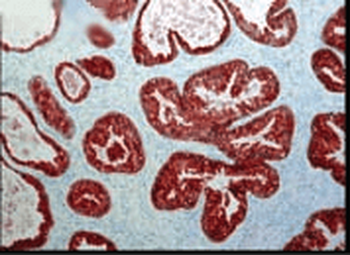

10 μg, 100 μgCYPA Rabbit Polyclonal Antibody [orb100498]

FC, IF, IHC-Fr, IHC-P, WB

Bovine, Canine, Porcine, Rabbit

Human, Mouse, Rat

Rabbit

Polyclonal

Unconjugated